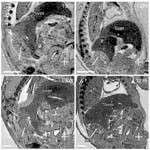

Caption: Histological analysis of Cited2tm1Ycy/Cited2tm1Ycy embryonic heart (details)

Represented Alleles:

Cited2tm1Ycy, Cbp/p300-interacting transactivator, with Glu/Asp-rich carboxy-terminal domain, 2; targeted mutation 1, Yu-Chung Yang

Copyright: This image is from Yin Z, Proc Natl Acad Sci U S A 2002 Aug 6;99(16):10488-93. Copyright 2002 National Academy of Sciences, U.S.A. J:78364